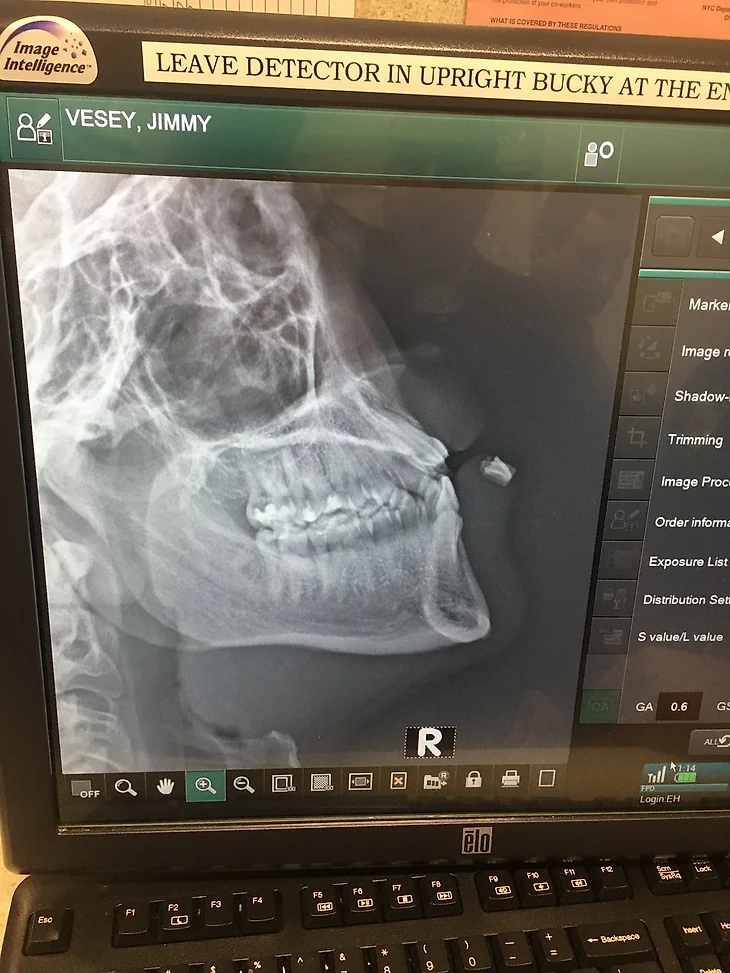

Как оказалось, зубы застряли в его губе... Гляньте на рентген.

После матча во время пресс-конференции тренер Рейнджерс Ален Виньо сообщил, что в губе застряли аж два зуба: "У него в губе сейчас два зуба... Врачам придется подумать, как их оттуда вытащить. Хокеей есть хоккей, верно?"